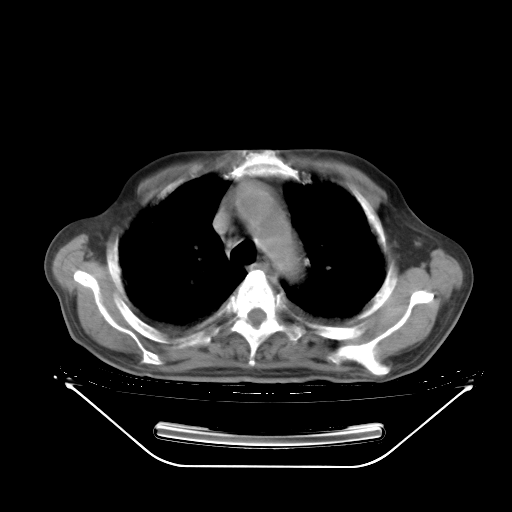

今天复查肺部CT,发现双肺广泛磨玻璃样改变。所以我把3月19日和5月9日相隔50天的肺部CT上传。请大家会诊。

2009年3月19日肺部CT片。

2009年3月19日肺部CT